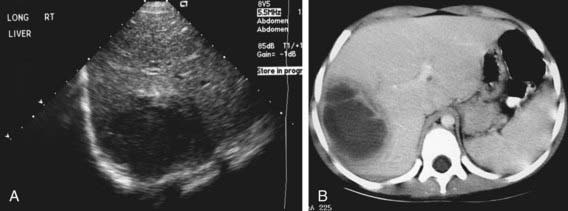

Figure 351-3 Amebic abscess. A, Sonogram demonstrates a hypoechogenic mass in the right lobe of the liver with a more hypoechoic surrounding rim. B, CT scan demonstrates a low-attenuation mass in the right lobe of the liver with a prominent halo.

(From Kuhn JP, Slovis TL, Haller JO: Caffrey’s pediatric diagnostic imaging, vol 2, ed 10, Philadelphia, 2004, Mosby, p 1473.)